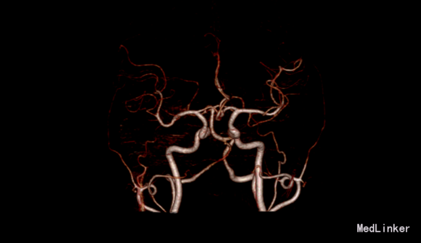

入院体检:T 36.9°C,P 87次/分,R 22次/分,BP 136/69mmHg。全身皮肤无黄染及出血点,全身浅表淋巴结未扪及肿大。双肺呼吸音清,未闻及干湿性罗音。心率87bpm,律齐,各瓣膜听诊区未闻及杂音。腹平,腹肌软,肝脾肋下未及,无压痛、反跳痛,肠鸣音正常。脊柱四肢无畸形,双下肢无水肿。神经系统:神清语晰,对答切题,记忆力、定向力、计算力正常,查体合作。双侧瞳孔等圆等大,直径约3mm,对光反射灵敏,双眼球活动自如,未见眼震。双侧额纹对称,双侧鼻唇沟对称,伸舌居中。四肢肌张力正常,左侧肢体肌力II级,指鼻试验、跟膝胫试验、闭目难立征未能配合检查。双侧腱反射对称存在,双侧巴氏征未引出。颈软,双侧克氏征、布氏征(-)。 辅助检查:生化:超敏C反应蛋白:2.6mg /l、乳酸脱氢酶(LDH):105U/L、甘油三酯(TG):2.32mmol/L、尿酸(URIC):416umol/L;同型半胱氨酸:14.3umol /l;D-二聚体定量:270ng /ml;糖化血红蛋白(HbA1c):5.1%;红细胞沉降率:3mm/h;人脂蛋白相关磷脂酶A2:378ng /ml;风湿十二项:(-); 胸部DR:主动脉硬化,双肺未见异常。心脏彩超:LVEF:66%。心内结构未见异常。 心内未见异常血流。 左室舒张功能降低。颈血管彩超:双侧颈总动脉、颈内动脉、颈外动脉、椎动脉未见异常。 双侧颈动脉、椎动脉血流速度正常。 急诊CT未见明显异常。 头颅MR:1、 双侧额叶软化灶,病灶周边少许胶质增生;2、MRA示未见明显异常。 头颅CTA:双侧颈内动脉虹吸段、双侧大脑中动脉、双侧大脑前动脉及其分支管壁尚规则,管腔通畅未见明显狭窄;右侧椎动脉颅内段管腔较左侧稍细小,余椎动脉、基底动脉及双侧大脑后动脉管腔未见明显变窄。大脑willis动脉环清晰显示,未见明显异常。 头颅CTV:大脑静脉系统上矢状窦、窦汇、横窦、乙状窦、直窦、大脑大静脉和颈内静脉管壁规则,管腔通畅未见狭窄、畸形等异常。 动态心电图示:1.窦性心动过缓;2.偶发室性早搏;3.偶发房性早搏;4.提示不完全性右束支阻滞;5.T波改变(心率快时);6.心率变异性:正常。 脑电图无异常。